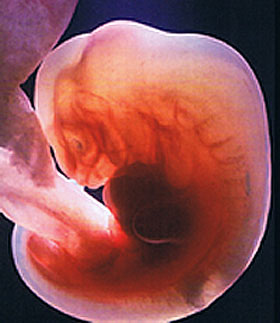

Как развивается и выглядит эмбрион на 4 неделе

Зародыш сейчас напоминает маковое зернышко: в нем не больше 1 мм и 0,5 грамм. На снимке УЗИ можно различить лишь небольшое темное пятнышко. Но несмотря на скромные размеры в нем уже заложены основы для развития всех органов и систем.

На четвертой неделе формируются первичные кровеносные сосуды, и ребенок сможет получать кислород. Закладывается амнион – одна из зародышевых оболочек, наполненная жидкостью, из которой позже образуется плодный пузырь.

Что развивается на четвертой неделе беременности

В начале этой недели плод начинает превращаться в эмбрион. Внешне он напоминает плоский, трехслойный диск, каждый из слоев которого станет основой для формирования органов и систем ребенка.

Так, из внутреннего слоя появляются поджелудочная железа, пищеварительная система, легкие, печень. Средний слой формирует сердце, кровеносные сосуды, почки, мышцы, скелет. Из внешнего слоя развиваются глазные хрусталики, волосы, зубная эмаль, нервная система, голова, кожа.

Размер плода на 4 неделе беременности равен 2 мм. Несмотря на такие микроскопические размеры, эмбрион очень бурно развивается. Появляются внезародышевые органы (желточный мешок, амнион, хорион), которые отвечают за обеспечение плода дыханием, питанием, оказывают ему биохимическую поддержку и защищают ребенка до тех пор, пока из амниона не сформируется плодный пузырь, а из хориона плацента.